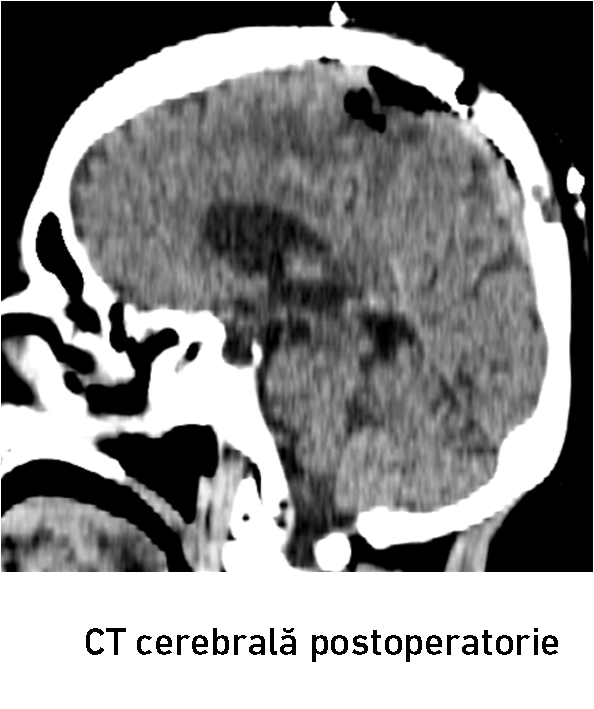

După 2 ore de la tratamentul endovascular, echipa chirurgicală a dat startul intervenției convenționale prin craniotomie osteoplastică. Grație embolizării preoperatorii, hemoragia intraoperatorie a fost redusă până la 500 ml. A fost realizată ablația totală macroscopică a meningiomului cu coagularea atașamentului dural, fapt confirmat prin CT cerebrală postoperatorie (fig. 8-10). Intervenția a fost efectuată de colaboratorii IMSP Spitalul Clinic Republican formată din conf. univ. d.ș.m. Eduard Eftodiev, dr. Alexandru Șumleanschi, dr. Iana Cotorcea, asistenta anestezistă Doina Dragan, asistentele de operație Maria Mutelică și Macela Cucheev. Toate obiectivele propuse au fost realizate cu succes de către echipa neurochirurgicală. Bolnava a fost externată la ziua 9-a postoperator în stare satisfăcătoare. Starea pacientei s-a ameliorat după tratamentul combinat : a regresat hemipareza în membrele drepte, pacienta devenind autonomă (Karnofsky PS 70%). Cu toate că bolnava a recuperat spectaculos forța în membrele hemicorpului drept, a fost recomandat continuarea tratamentului de recuperare şi neuroreabilitare.

După 2 ore de la tratamentul endovascular, echipa chirurgicală a dat startul intervenției convenționale prin craniotomie osteoplastică. Grație embolizării preoperatorii, hemoragia intraoperatorie a fost redusă până la 500 ml. A fost realizată ablația totală macroscopică a meningiomului cu coagularea atașamentului dural, fapt confirmat prin CT cerebrală postoperatorie (fig. 8-10). Intervenția a fost efectuată de colaboratorii IMSP Spitalul Clinic Republican formată din conf. univ. d.ș.m. Eduard Eftodiev, dr. Alexandru Șumleanschi, dr. Iana Cotorcea, asistenta anestezistă Doina Dragan, asistentele de operație Maria Mutelică și Macela Cucheev. Toate obiectivele propuse au fost realizate cu succes de către echipa neurochirurgicală. Bolnava a fost externată la ziua 9-a postoperator în stare satisfăcătoare. Starea pacientei s-a ameliorat după tratamentul combinat : a regresat hemipareza în membrele drepte, pacienta devenind autonomă (Karnofsky PS 70%). Cu toate că bolnava a recuperat spectaculos forța în membrele hemicorpului drept, a fost recomandat continuarea tratamentului de recuperare şi neuroreabilitare.